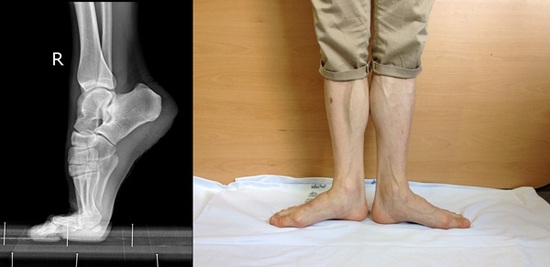

게다가 남들이 하지 않는 바깥쪽 수평으로 벌린 채 서는 ‘턴아웃(turn-out)’(사진 오른쪽) 자세와 발 끝으로 서는 ‘포인트(pointe)’(사진 왼쪽) 자세가 기본 동작이 돼 있다. 이 동작들은 해부학적으로 매우 불편한 자세라 일반인은 사실상 수행하기가 불가능하다. 이 때문에 대부분의 무용수들은 발에 무리가 가는 족부 질환을 안고 지낸다. 따라서 ‘무용’ 자체를 이해하지 않고서는 무용수들을 치료한다는 것은 사실상 어려움이 있다.